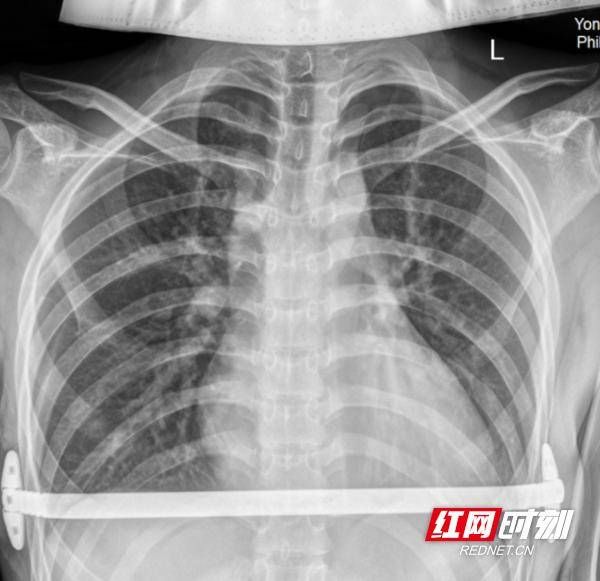

術(shù)后X片。

術(shù)后,醫(yī)院發(fā)揮中西醫(yī)協(xié)同康復(fù)特色,西醫(yī)精準治療+中醫(yī)辨證調(diào)理、穴位按摩、膳食指導(dǎo),加速傷口愈合、減輕術(shù)后不適?;颊呋謴?fù)迅速,無并發(fā)癥,胸廓形態(tài)恢復(fù)正常,心肺壓迫完全解除,重拾挺拔身姿與陽光心態(tài)。